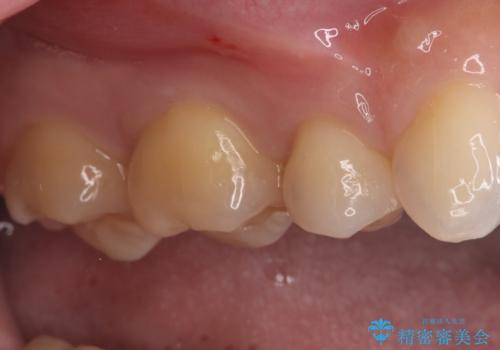

後日、歯の色調に合わせてオーダーメイドで作製されたセラミックインレーを装着。セラミックは天然歯のような透明感があるため、修復した箇所がどこかわからないほど自然な仕上がりとなりました。

また、セラミックは汚れ(プラーク)が付きにくく、経年劣化による変色もほとんどないため、再発リスクを抑えつつ、長期的に白く美しい状態を維持することが可能です。機能・審美の両面で、患者様にご満足いただける結果となりました。